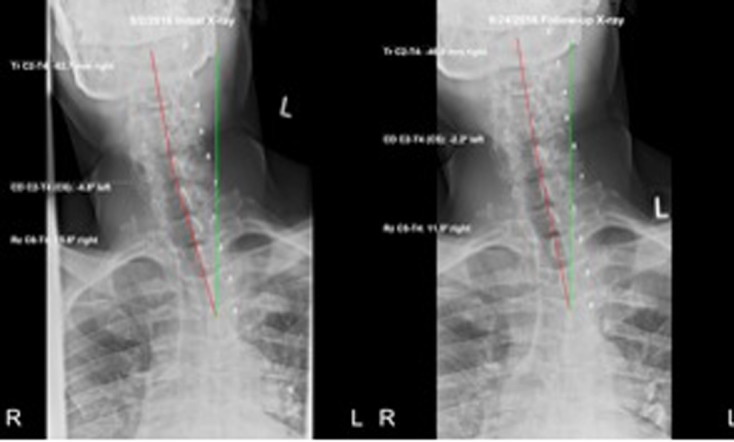

Posture analysis (Figure 1) as outlined by Harrison [6] revealed a forward head position, a prominent right head translation, a forward translated thorax, a right translated thorax, and a right laterally tilted pelvis.

The lateral full-spine radiograph (Figure 2) demonstrated a significant forward lean, as the measurement from the horizontal distance from the posterior-superior vertebral body corner of T1 to the posterior inferior body corner of S1 measured 192.3 mm (ideal=0 mm. [10] The lateral cervical specific image (Figure 3) demonstrated a forward head position of 67.5 mm (normal=0–15 mm [11]), an ARA from C2–C7 of –29.6° (normal= –31° to 42° [11–13]), and an atlas plane angle of –7.6° (normal= –29° [11, 12]). The AP cervico-thoracic view (Figure 4) showed a large right head translation (62.7 mm; normal=0 mm [10]), with a cervico-dorsal angle of –4.8° (normal=0° [10]) and an Rz angle of 15.6° (normal=0° [10]). The AP lumbar view (Figure 5) showed a right thoracic translation (–12.6 mm; normal=0 mm [10]), with unleveling of the pelvis lower on the right.

The patient’s posture as seen visually (Figure 1) improved dramatically. Follow-up radiographic assessment confirmed and quantified the significant improvements in the patient’s posture (Figures. 3–6).

The total body forward shift from T1-S1 reduced (132 mm vs. 192 mm),

forward head posture reduced (36.5 mm vs. 67.5mm),

there was an increased cervical lordosis (–37.2° vs. –29.6°),

an increased atlas plane angle (–19.8° vs. –7.6°),

a reduced lateral head translation (–46 mm vs. –62.7 mm) and

a reduced lateral thoracic translation (–2.4 mm vs. –12.8 mm).